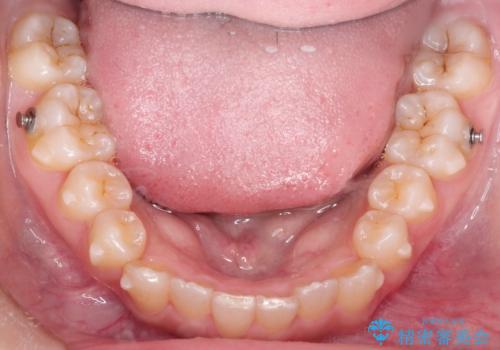

- 前歯のガタガタを主訴に来院された患者様です。

八重歯になっており、下顎の前歯が上顎の前歯に隠れてしまう、ディープバイトという状態でした。

インビザラインを使用して矯正する計画としました。

ディープバイトの場合、ワイヤー装置の装着が難しいことがあります。

インビザラインではかみ合わせに左右されず装着できるメリットがあり、ワイヤーに比べインビザラインの方が治療しやすい場合もあります。